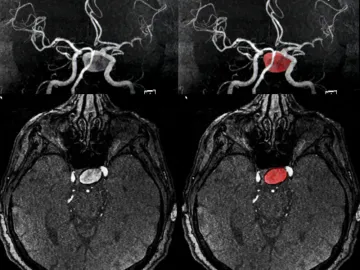

A los 18 años, Ella Pick experimentó lo que creyó ser un malestar producto de la resaca durante unas vacaciones con amigas. Sin embargo, al regresar a casa y retomar su rutina, sus síntomas se intensificaron. Migrañas persistentes y el hundimiento de su ojo izquierdo la llevaron a buscar ayuda médica, donde recibió la devastadora noticia de que tenía un tumor cerebral incurable e inoperable. Le dieron un pronóstico de vida de solo 12 meses.

Desde entonces, la vida de Ella quedó en pausa mientras asimilaba su diagnóstico y se preparaba para lo inevitable. A pesar del golpe devastador, Ella decidió mantener una actitud positiva y continuar con su vida lo mejor que pudo. Se sometió a un tratamiento de radioterapia en un esfuerzo por detener la progresión del tumor, y aunque en su última revisión se informó que el tumor estaba estable, ella sigue abierta a cualquier opción que pueda prolongar su tiempo.